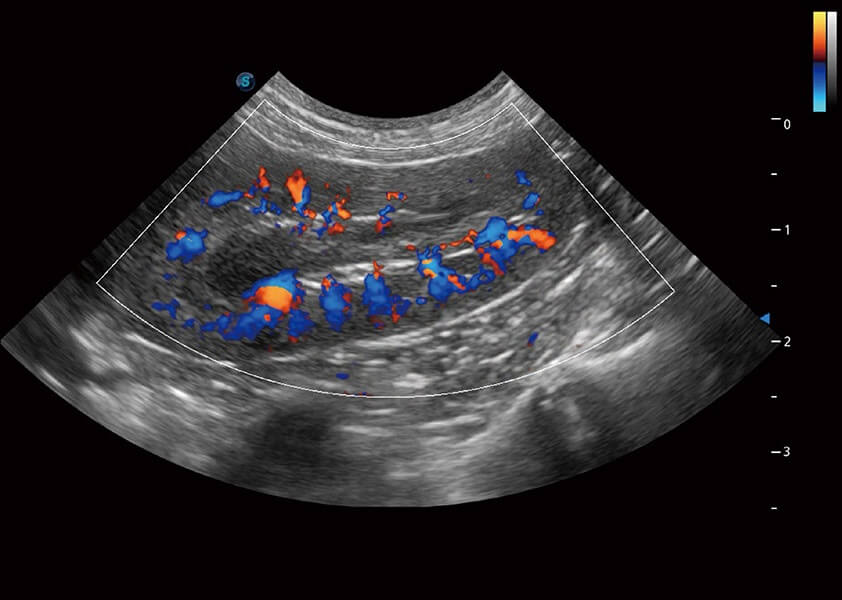

ProPet 60 作为一款高端台式动物超声设备,为动物医生的日常诊断提供了一系列贴合动物临床需求、解决临床实际问题的高级成像功能。凭借全系列高清探头,满足医生对腹部、心脏、生殖、浅表、肌骨等成像的所有需求,切实帮助您提升检查效率,提高诊断信心。

动物是人类最亲密的朋友和最值得信赖的伙伴。狗万官方网站也一直致力于探索动物专用的超声影像解决方案。 全新推出的ProPet系列,是狗万官方网站在动物超声影像智能化、专业化、精准化的一次跨越式革新。动物不能用言语来表述自己的不适,通过超声影像,ProPet系列搭建了动物医生与不同物种沟通的“桥梁”,为动物医生注入了“治愈之力”。